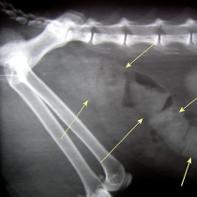

Thanks to advancements in veterinary care, our dogs and cats are living longer than ever before. This is great news! But this also means that they can develop some of the same diseases that affect older people. Osteoarthritis, also called degenerative joint disease or arthritis, can have an enormous impact on quality of life for dogs and cats. Arthritis causes pain, restricts movement, and causes joint swelling. You may first notice that your dog does not get up as easily as he used to. He may appear stiff or lame. He may lick or chew at affected joints. Signs of arthritis may not be noticed immediately.